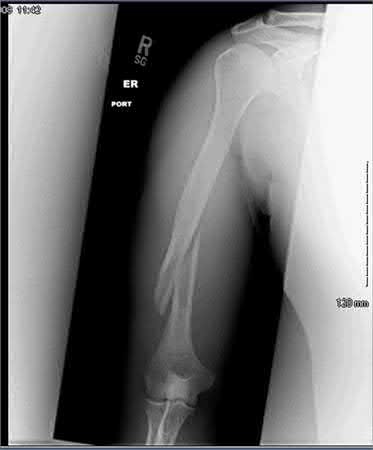

Question 21:

Correct Answer: Wide local excision with margins

This patient has a Grade II (intermediate grade) chondrosarcoma of the proximal humerus. Chondrosarcomas are largely resistant to traditional chemotherapy and radiation therapy. High-grade (Grade II and III) chondrosarcomas, as well as those in the pelvis or proximal appendicular skeleton, require wide local excision with negative margins to minimize local recurrence. Intralesional curettage is reserved for benign enchondromas or selected Grade I (low-grade) chondrosarcomas in the appendicular skeleton.